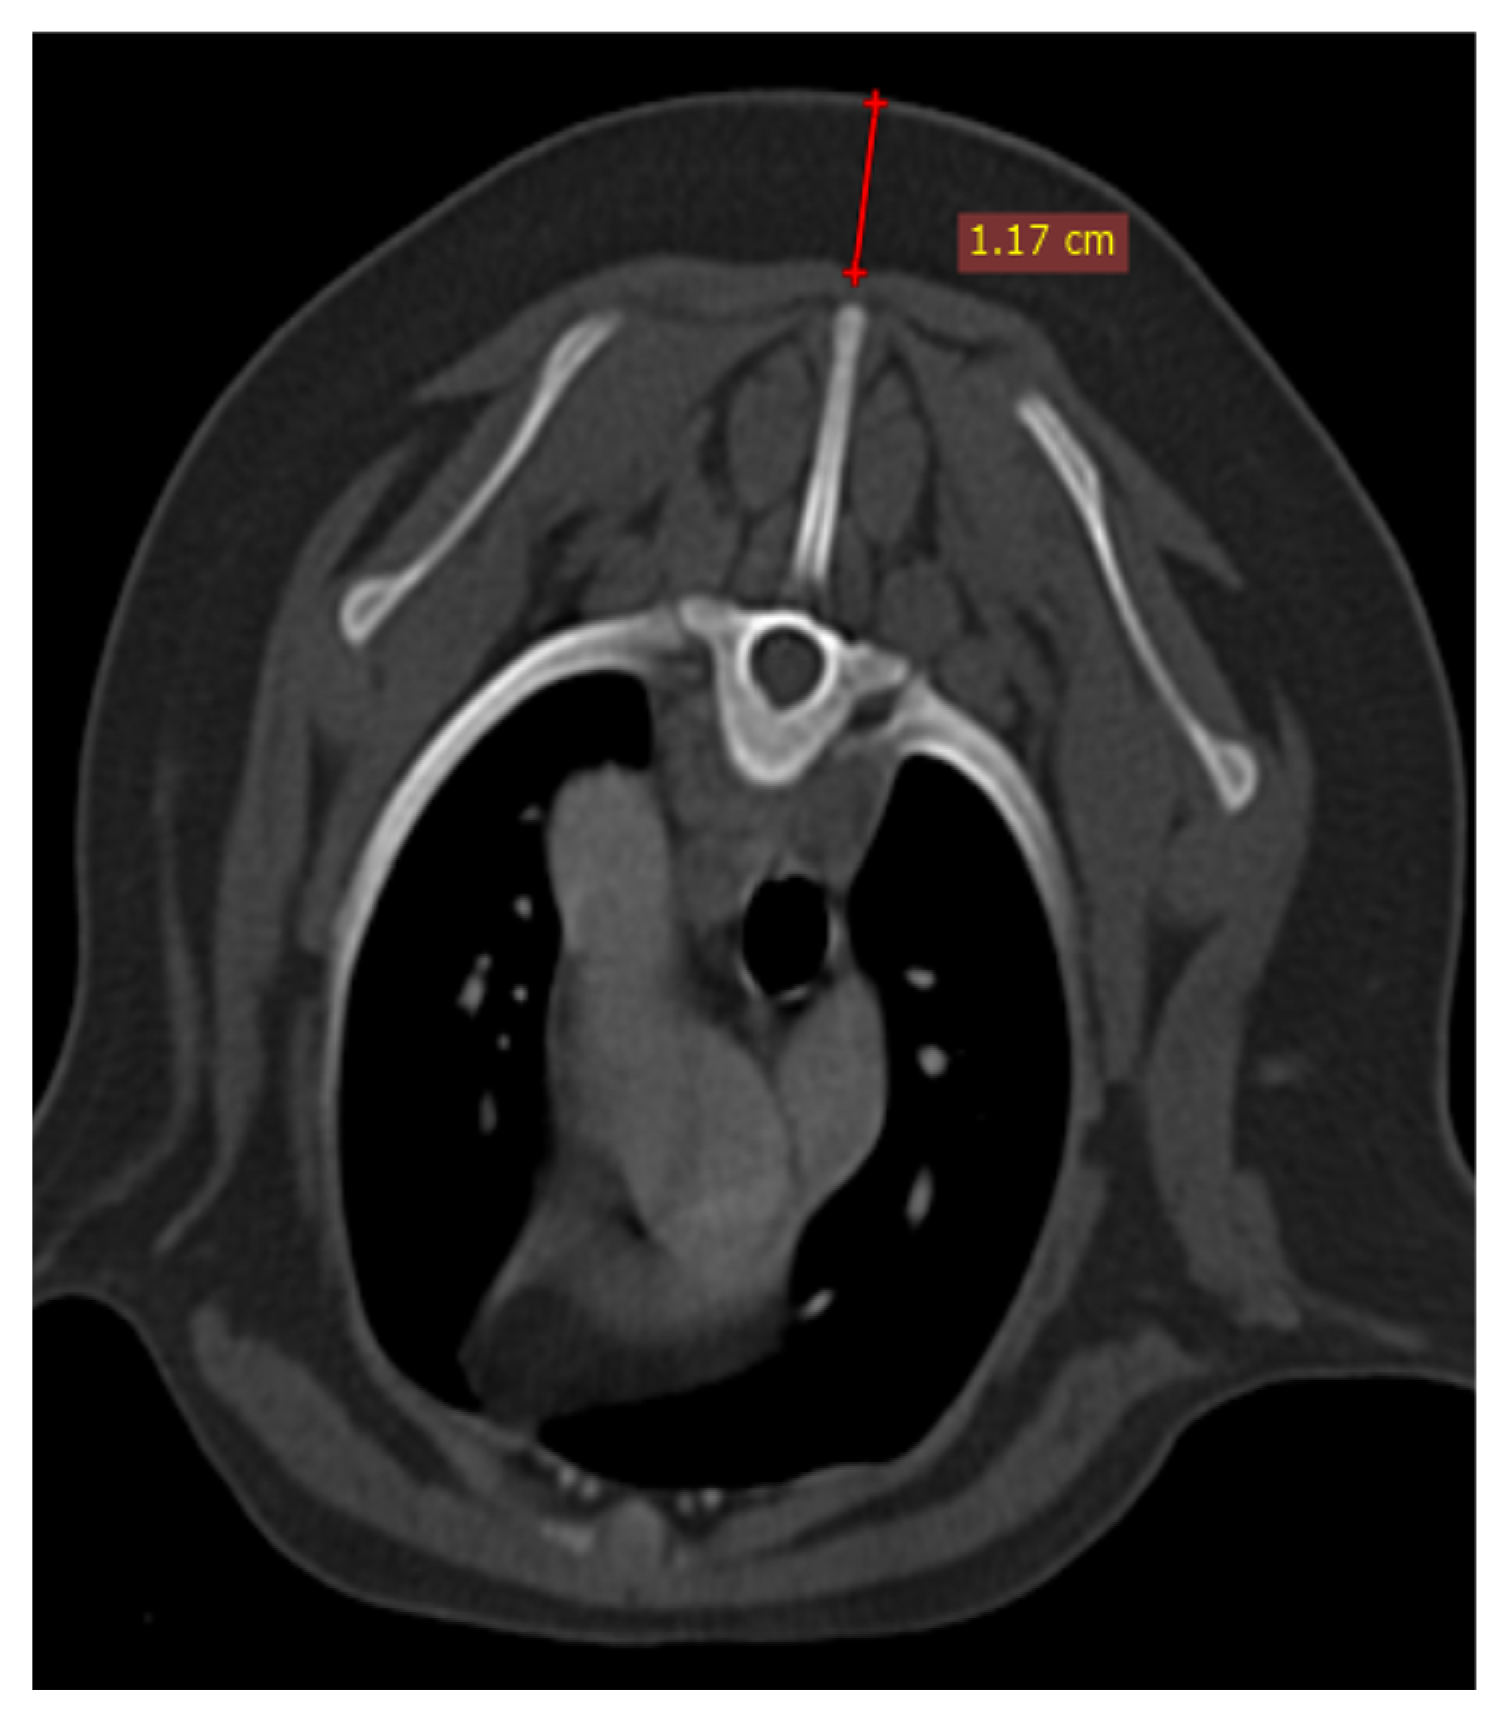

The size of the thymus was also measured in transverse and dorsal images. The maximum height (TH) and diameter (TD) in transverse images and maximum diameter (DD) and length (DL) in the dorsal view were measured (Figure 3 and Figure 4), as well as thymic volume (TV) in all groups. These indices were measured in the area related to mediastinal fat at the normal location of the thymus for patients with a completely fatty replacement of the thymus (grade-0). All measurements were done in contrast-enhanced examinations. To normalize the thickness of the thymus gland in transverse view, the width of the second thoracic vertebra midbody was measured and the ratio was calculated. The correlation between thymic size and grade with the body fat content was evaluated by measuring the thickness of subcutaneous fat in the dorsal aspect of the T4 spinous process (Figure 5). Subjective characteristics such as predominant deviation of the thymus to left or midline position, the thymic shape (wedge-shape, rectangular-shape, or linear-shape), and the thymic contour (convex and concave) were also evaluated. For patients with fatty degeneration, these characteristics were analyzed in mediastinal fat at the location of the previous thymus. Evaluation of thymic size, volume, attenuation, and grade was done twice by a single person within a week, and the mean value of the first and second measurements for numerical data and the second results for thymic grading were reported.

Figure 5. Demonstration of Measurement of Subcutaneous Fat Content at the Level of T4 in Transverse Section of Post-Contrast CT Examination.